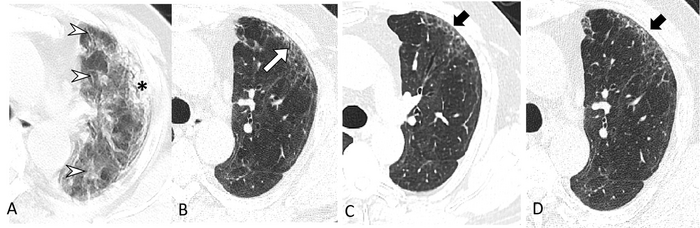

图像:一名65岁严重COVID-19男性的连续横向CT扫描。(A)症状出现后第23天的CT扫描显示左侧上叶弥漫性磨玻璃影(箭头)伴胸膜下实变(*)。(B)随访6个月时的图像显示左肺前上叶胸膜下主要为毛玻璃影,伴轻度支气管扩张(白色箭头)。(C, D)随访12个月和2年的图像显示在同一区域存在细微的胸膜下蜂窝(黑色箭头)。该患者主诉持续的劳力性呼吸困难,在2年的随访中显示肺对一氧化碳的轻度扩散能力(74%)。